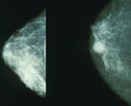

In the initial stages of the study the team used mammogram images to compare similar abnormalities in the new 3D image produced from the radio breast imaging system.

In the coming months the team plan on "testing blind", this means looking at images taken by both machines and examining each independently to check whether the radio breast imaging system's 3D image picks up the same abnormalities as a mammogram would and if anything else is identified in the new image.